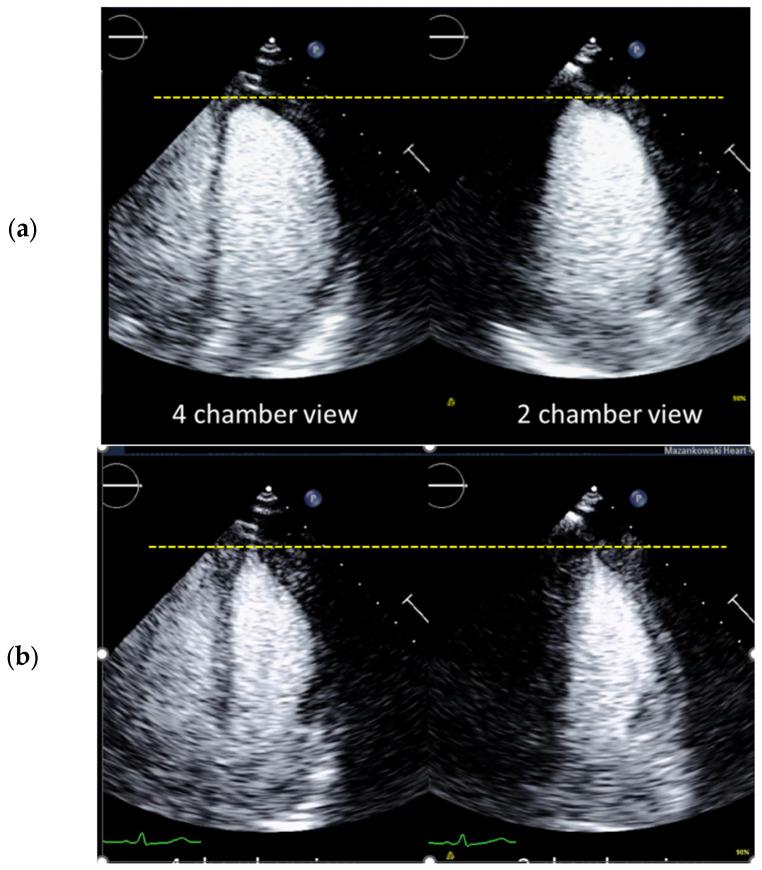

How to Perform Cardiac Contrast-Enhanced Ultrasound (cCEUS): Part I.

Ultrasound enhancing agents (UEAs, formerly called contrast agents) for assessments of the left heart have improved the applicability of echocardiography and the accuracy of echocardiographic measurements. UEAs have been recommended for several diagnostic echocardiographic procedures by national and supernational agencies. The increased use of UEAs during the last years provided more evidence and experience in clinical practice data which is helpful for optimizing the UEA procedures and which will be useful for both newcomers to UEA in echocardiography and sonographers/physicians with experience in echocardiography with UEAs. In two parts, this review focuses on the "how to do" for the approved UEA applications. This is part 1, covering the available UEAs and providing specific guidance on the assessment of global and regional LV function. Part 2 covers the imaging of myocardial disease and masses as well as myocardial perfusion. Recommendations include the application of UEAs in two-dimensional echocardiography as there is limited data on three-dimensional echocardiography. A step-by-step approach is proposed for each of the procedures as well as guidance on how to interpret recordings and how to report them.